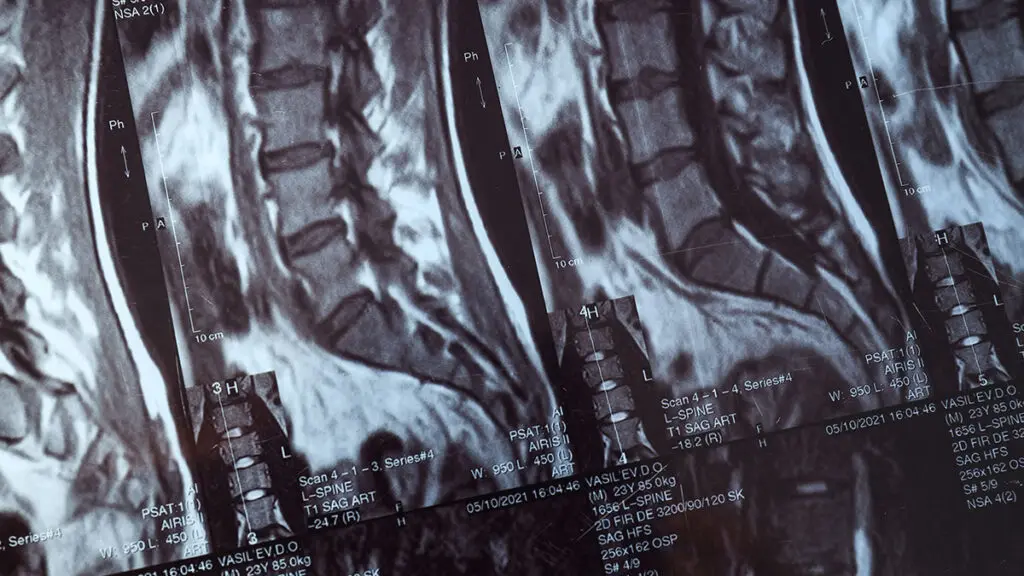

Global Spine Solutions è il centro terapia del dolore di eccellenza della capitale, specializzato in neurochirurgia spinale mininvasiva. Il nostro team multidisciplinare opera con tecnologie all'avanguardia per diagnosi accurate e trattamenti efficaci di tutte le principali patologie vertebrali, dal dolore lombare cronico alle condizioni neurologiche più complesse.

Come centro terapia del dolore, Global Spine Solutions accompagna il paziente lungo l'intero percorso di cura: dalla prima valutazione clinica, attraverso la pianificazione del trattamento conservativo o chirurgico, fino alla riabilitazione post-operatoria, garantendo continuità assistenziale e risultati misurabili.